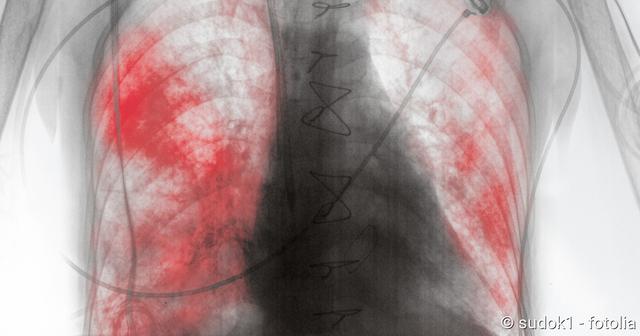

Bei der körperlichen Untersuchung kann der Arzt ein schabendes oder knarrendes Geräusch beim Abhören des Brustkorbs feststellen, das durch die Reibung der entzündeten Brustfellteile entsteht. Bildgebende Verfahren wie Röntgenaufnahmen oder eine Computertomographie können helfen, die Diagnose zu bestätigen und den Zustand des Rippenfells genauer zu beurteilen.

– Eine Lungenentzündung kann durch Röntgenaufnahmen oder eine Computertomographie (CT) des Brustkorbs diagnostiziert werden.